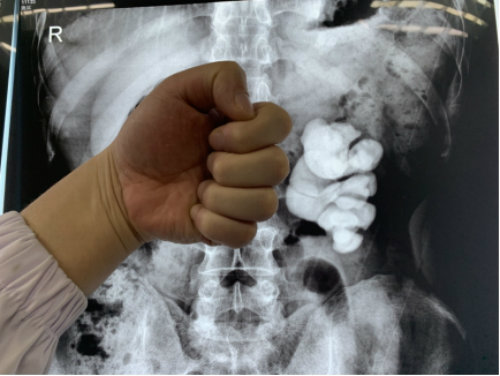

2019年11月26日,湖北蘄春的周先生在武漢京都結(jié)石醫(yī)院成功保腎取出左腎里近十公分的拳頭大結(jié)石,堪稱微創(chuàng)取石領(lǐng)域的典范案例。

跟絕大多數(shù)腎結(jié)石患者一樣,周先生在發(fā)現(xiàn)結(jié)石之前,沒(méi)有體檢的習(xí)慣,偶爾的腰脹腰痛問(wèn)題,也總在當(dāng)腰椎病在治。結(jié)果差點(diǎn)把腎給“耽誤”了。

據(jù)他本人回憶,最早發(fā)現(xiàn)左腎被結(jié)石撐滿是在11月3日,當(dāng)?shù)亟釉\醫(yī)生叫他做好手術(shù)準(zhǔn)備,隨時(shí)可能要切腎。不相信問(wèn)題嚴(yán)重性的他又找到另外一位醫(yī)生,當(dāng)?shù)诙会t(yī)生也給出了同樣的答復(fù)后,他開(kāi)始心灰意冷了。

近日,周先生慕名趕到專門(mén)治結(jié)石的武漢京都結(jié)石醫(yī)院。完善相關(guān)檢查后,醫(yī)生初步判定其左腎還有部分功能,決定為他放手一搏。盡管手術(shù)難度大,術(shù)中出現(xiàn)大出血和腎內(nèi)壓過(guò)高導(dǎo)致的穿刺時(shí)腎破裂的概率極高,但在該院多科室專家的全力救治下,周先生最終如愿保住了左腎,拳頭大的結(jié)石也被處理了。

醫(yī)生提醒,腎結(jié)石和腰椎病癥狀有相似之處,市民如無(wú)法自行判斷,可到專業(yè)醫(yī)院做泌尿系彩超、腰椎ct等加以區(qū)分,切勿顧此失彼。